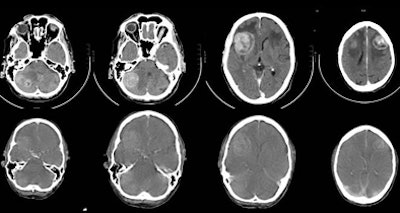

| Comparison of dedicated CT of the brain (CT1) versus the CT component of PET/CT (CT2) shows no statistically significant difference between these two CT scans in detecting malignant brain lesions, despite the fact that the quality of the CT of the brain in the PET/CT study is inferior. |